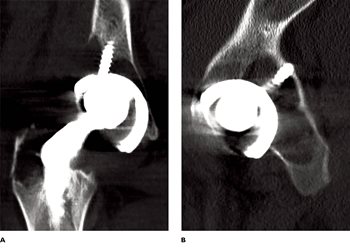

The wearing process in polyethylene liners produces small particles of polyethylene debris. The immune system responds by releasing macrophages and associated cytokines (e.g. TNF-α), which activate osteoclasts that produce osteolysis around the hip joint (Fig. 3).

Fig. 3. CT scan coronal (A) and axial (B) images showing significant osteolysis behind

the previously implanted acetabular cup.

The loss of bone causes micromotion of the hip implants, and further potentiates osteolysis. As a result of the osteolysis and wear, patients are at increased risk of several consequences, including periprosthetic fractures from simple falls or minor trauma, aseptic loosening of the prosthesis, or dislocation of the prosthesis.